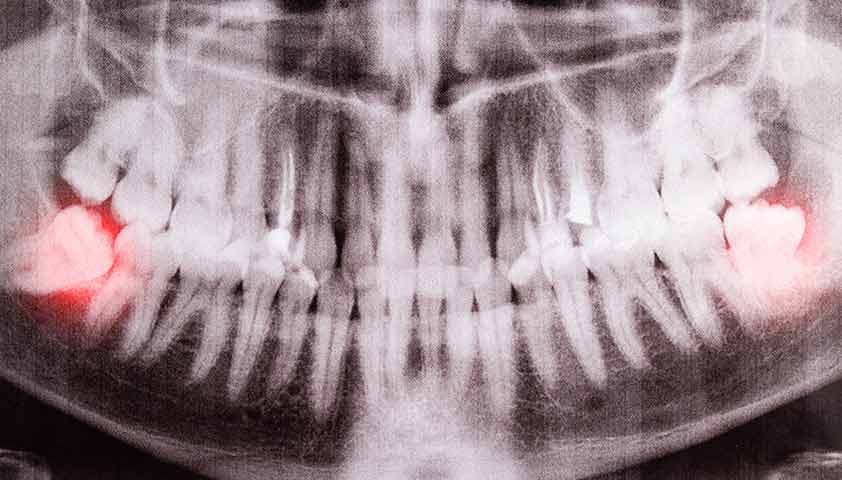

По рентгенограмме определяется прикорневая киста зуба как округлая очаг разрежения костной ткани. Кисты, размером более 1 см, считаются кистами, при размере от 0,6 до 1 см — кистогранулемами, а при размере 0,5 см — гранулемами.

Рентгенографическое обследование зубочелюстной системы помогает обнаружить кисту зуба. Она выглядит на изображении как четко очерченная полость округлой формы на вершине корня зуба. Более точную информацию о размерах и положении кисты можно получить с помощью трехмерной компьютерной томографии. Однако исследования назначает только врач-стоматолог после осмотра полости рта и опроса пациента о его симптомах и жалобах.

В процессе подготовки к протезированию или имплантации, стоматологи часто выявляют новообразования у пациентов, когда делают панорамный снимок лица.